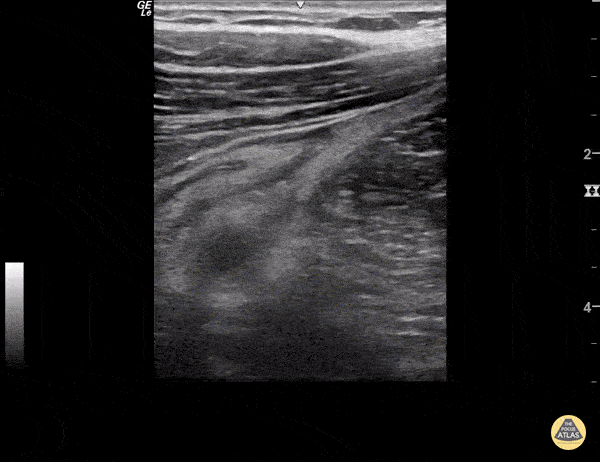

Bowel-GI - Retrocecal Appendicitis

A non-compressible appendix with appendicolith is seen with surrounding fat stranding posterior to a decompressed cecum. Sukh Singh, MD